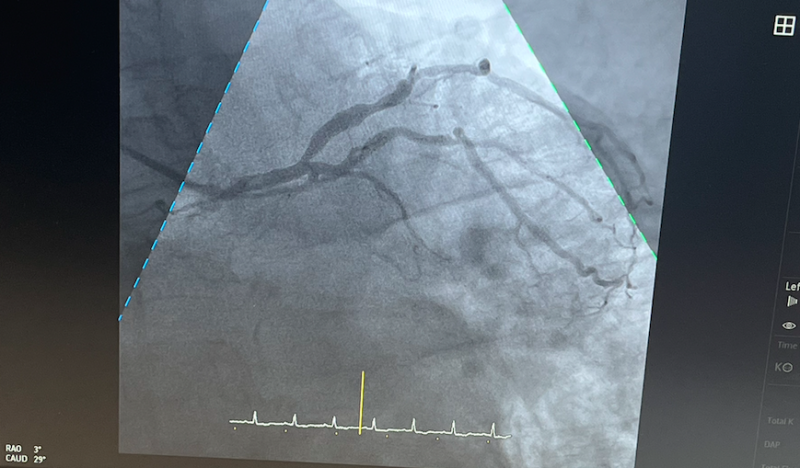

В ФГБУЗ «ММЦ имени Н.И.Пирогова» ФМБА России в Мурманске выполнены первые коронарографии, высокотехнологичные лечебно-диагностические вмешательства состоялись в новом операционном блоке на установленном ангиографе фирмы Philips Azurion 5F20.

Коронарография - это метод контрастного рентгенологического исследования сосудов сердца, при котором в кровеносное русло вводится специальный рентген-контрастный препарат, благодаря чему сосуды становятся видимы на рентгенографии.

- Это облегчает визуализацию артерий, что помогает врачам получить полную картину состояния сосудов пациента: их проходимости, наличия или отсутствия тромбов, и т.д. Он позволяет с высочайшей точностью определить локализацию сосудистой патологии и принять наиболее точное решение о тактике дальнейшего лечения пациента, - пояснили в медицинском учреждении.

Первым пациентом центра стал мужчина 70-ти лет, у которого, благодаря выполненной коронарографии, было выявлено сосудистое поражение коронарного русла артерии, снабжающей сердце. Оказалось, что у пациента поражены несколько артерий, и формируется аневризма левого желудочка.